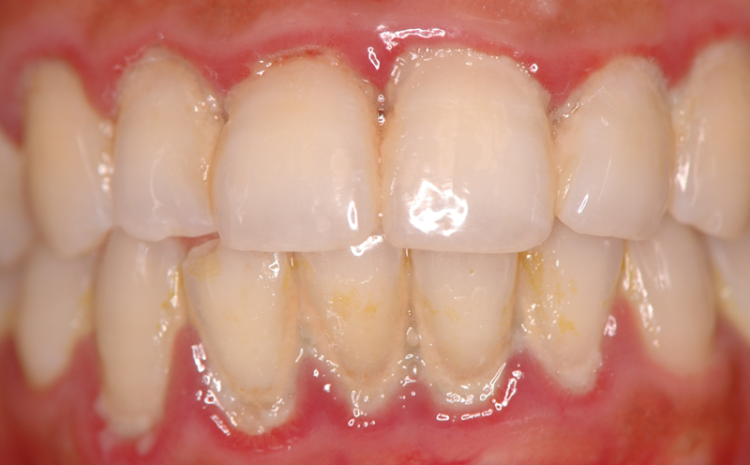

우리가 음식을 섭취하다 보면 구강에는 타액과 세균이 서로 융합이 되면서 플라크라고 하는 얇은 세균 막이 켜켜이 쌓이게 되는데요.

3232235521_53QCocEq_30a7872a49df8f23f856d30079f1f25f96459cc0.png3232235521_CVHQzo9s_b267358bdb708003317b9f202741d2ce0e3bd5d4.png 이때 이 플라크가 제대로 제거되지 않고 음식물과 섞여 단단하게 굳어지게 되면 쉽게 제거되지 않는 단단한 세균 덩어리로 바뀌게 되는데 이를 치석이라고 합니다.